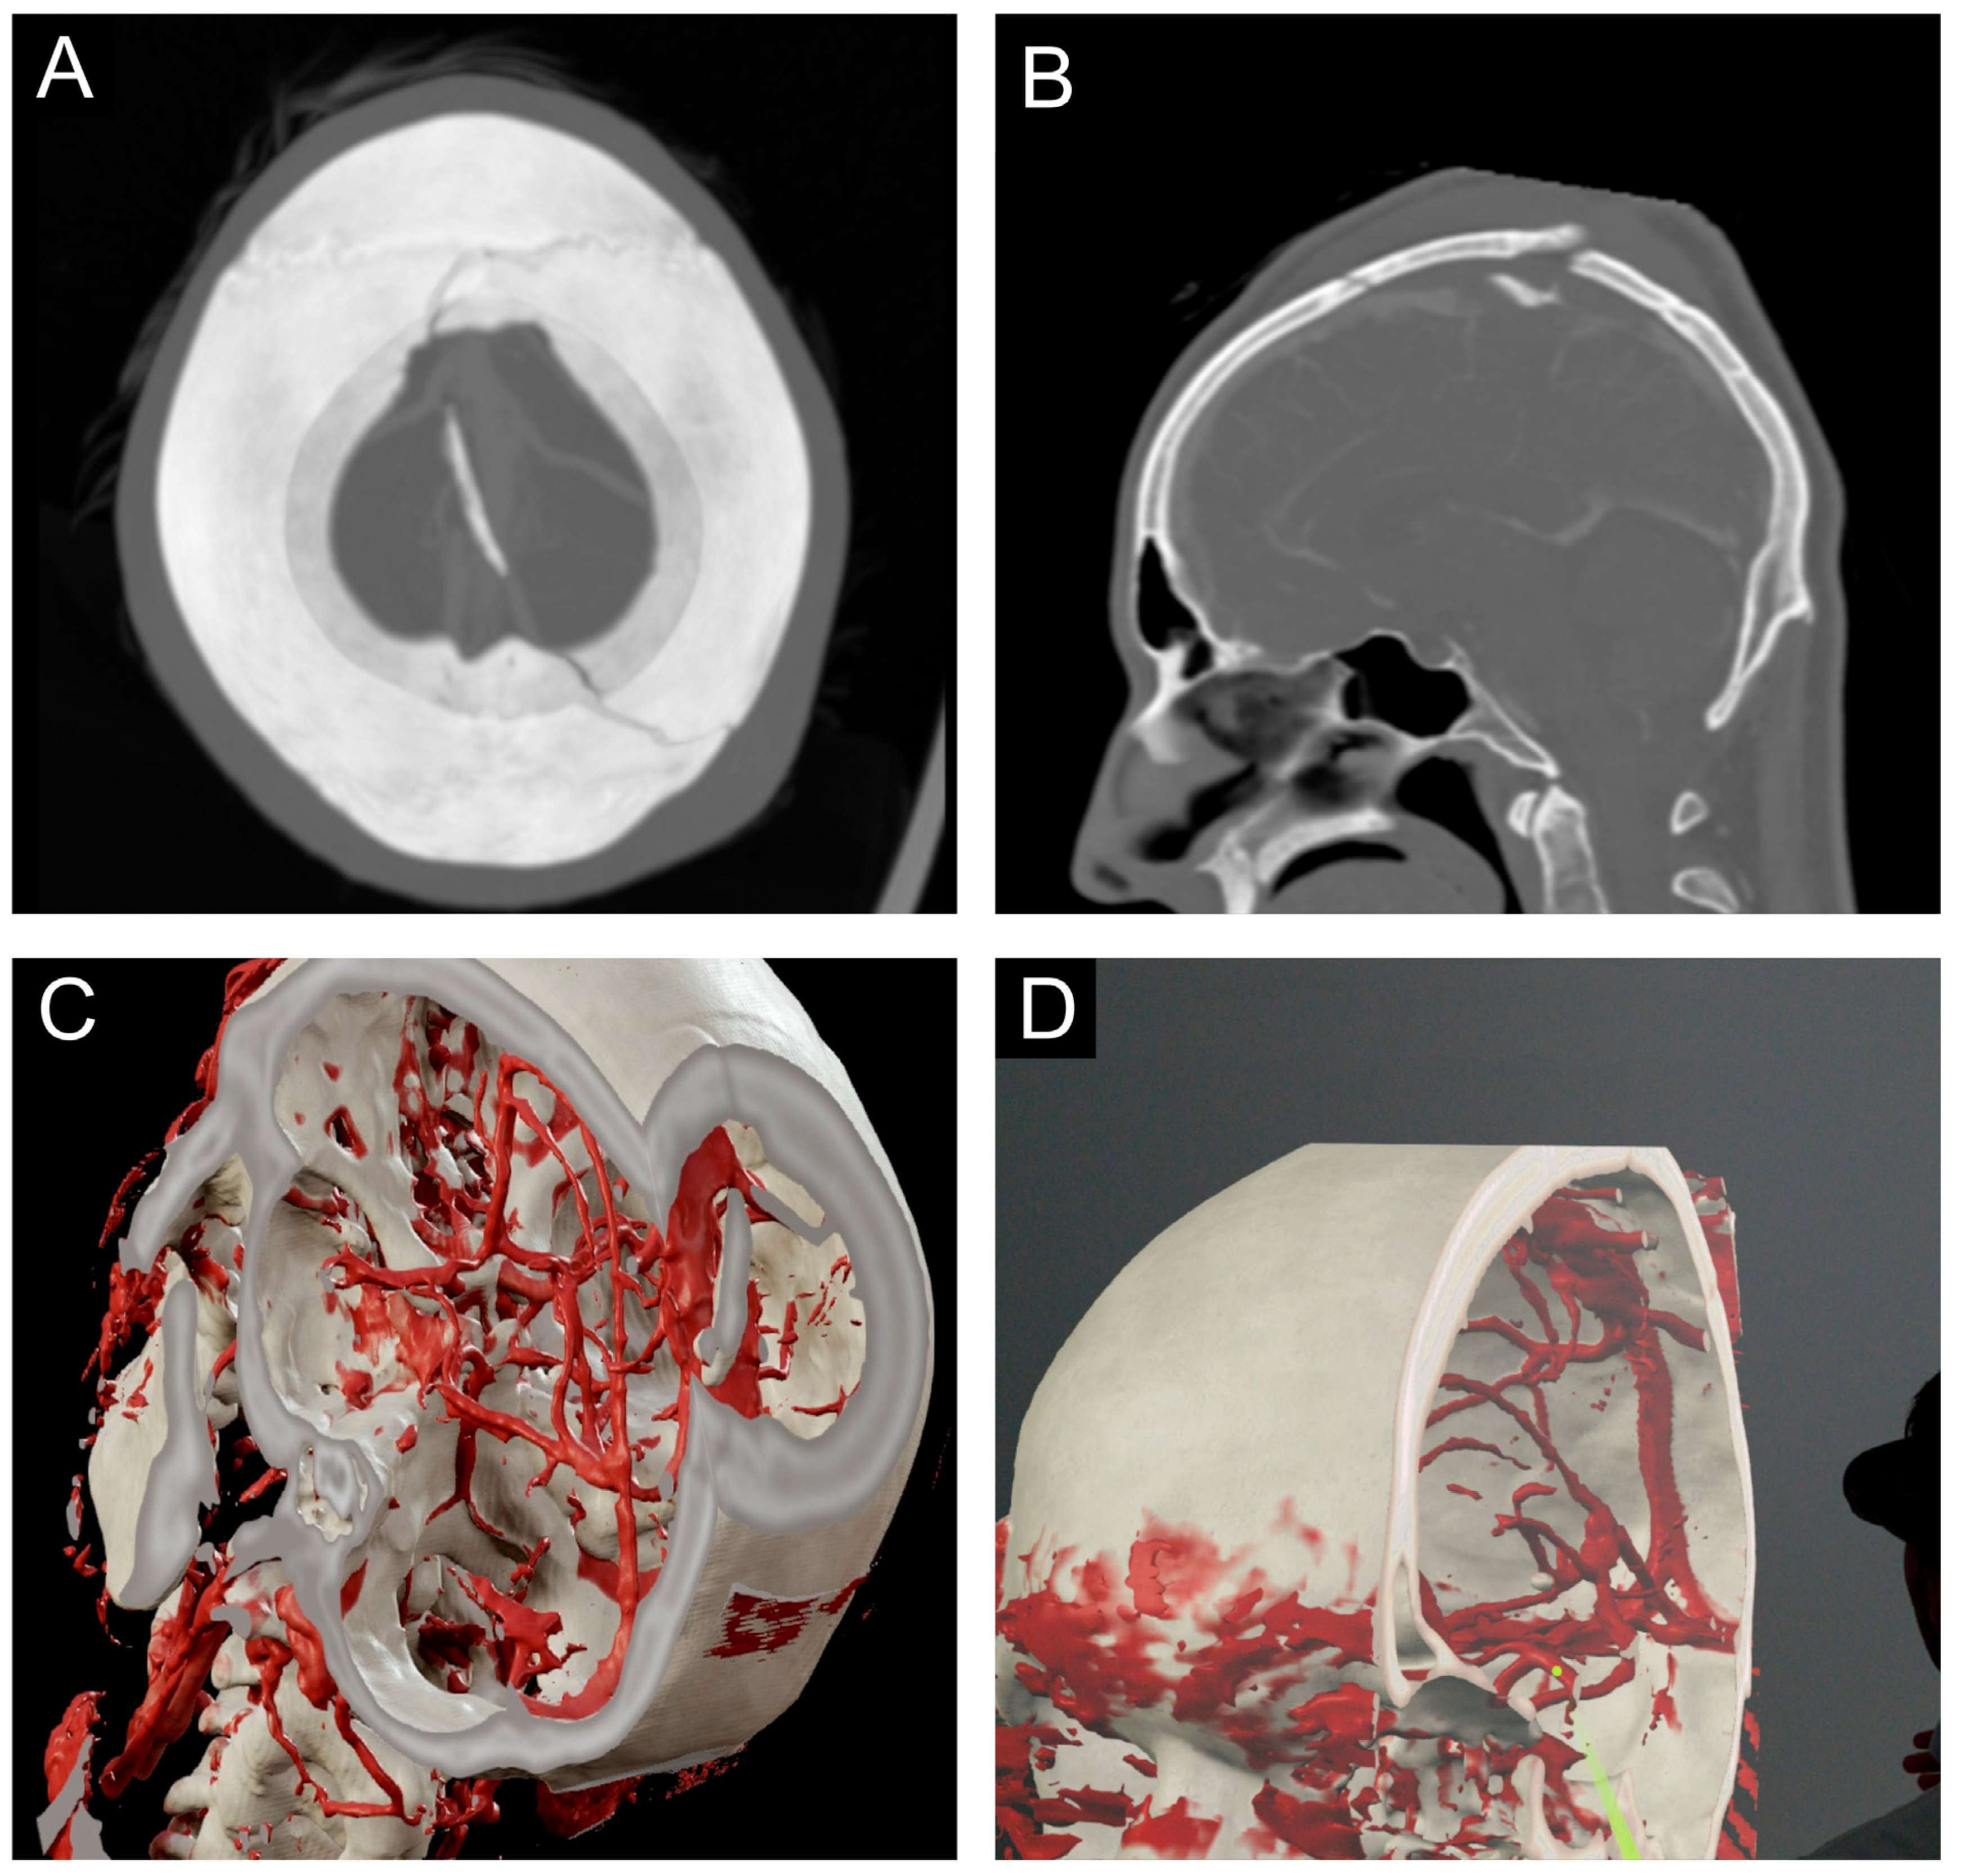

2.4. Prepared Case

2.5. Technical Setup